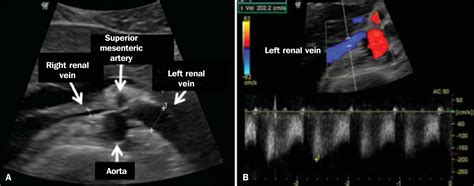

To grasp the mechanical nature of this condition, it is helpful to visualize the anatomy of the abdomen. The left renal vein travels horizontally across the abdomen to deliver blood from the left kidney into the inferior vena cava. In patients with Nutcracker Syndrome, the angle at which the superior mesenteric artery branches off the aorta is unusually narrow. This anatomical narrowing acts like a clamp, compressing the renal vein.

When the vein is compressed, the blood cannot flow freely. This results in high venous pressure, which can cause the vein to become dilated or distended. Furthermore, this back pressure often leads to the development of varicocele (enlarged veins in the scrotum) in men or pelvic congestion syndrome in women. Because this involves structural anatomy, it is a mechanical issue rather than a lifestyle-related disease, which is why it often requires specialized vascular consultation for proper management.

Diagnosing this condition requires advanced imaging techniques to visualize the vascular anatomy and confirm the compression. Doctors typically use a combination of non-invasive and invasive tests to determine the severity of the obstruction.

Doppler Ultrasound Evaluates blood flow velocity and identifies narrowing of the renal vein.